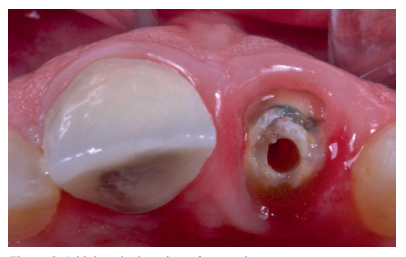

After anaesthetic infiltration (4% articaine with 1: 100,000 adrenaline), the root of the affected tooth was extracted. As a complication of the extraction, the distal papilla was lacerated, which was repaired with a single stitch. The residual socket was then evaluated to prepare the bed to insert the OII. This was intact, with intact vestibular cortex.

The OII (ETK-Naturactis™, 4 x 12 mm) was placed at a depth of 4 mm with respect to the future gingival margin that needed to be achieved. The margin of the provisional prosthesis was used as a reference, similar to the gingival margin of the adjacent central incisor that was maintained without recession.

Proper primary stability was obtained, with anchorage achieved in the residual palatal bone at an insertion torque of 40 N/cm2 . A periapical radiograph was performed to confirm the position (Figure 10).